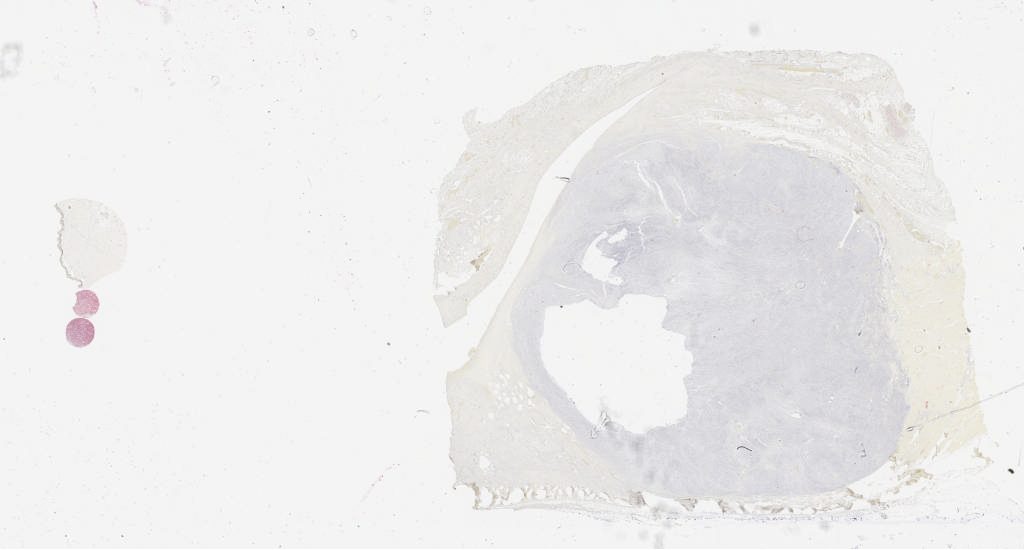

he.svs

89639

x

80322

@

40X